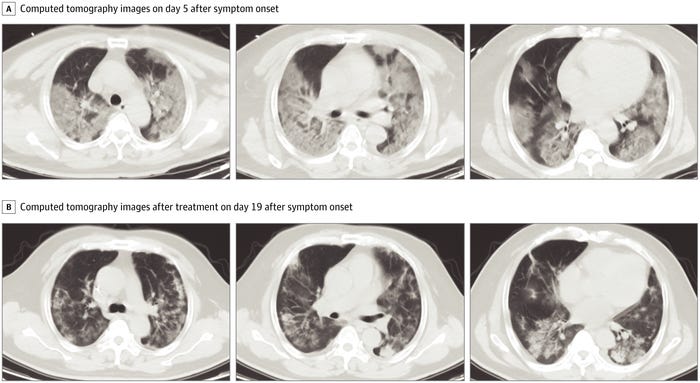

Cercetătorii au analizat scanările de la pacienții de la Spitalul Zhongnan din Universitatea Wuhan, majoritatea fiind bărbați mai în vârstă, cu probleme de sănătate preexistente. Imaginile de mai sus sunt scanări ale unui pacient de 52 de ani.

Primul grup de scanări (grupa A) au fost făcute pe 7 ianuarie, la cinci zile după ce pacientul a început să prezinte simptome. Ele prezintă „petele de sticlă măcinată” în partea de jos a ambilor plămâni.

În perioada 7 – 12 ianuarie bărbatul a putut respira doar cu ajutorul ventilatorului. După aceea, starea lui părea să se îmbunătățească. Al doilea set de scanări (grupul B), făcut pe 21 ianuarie, arată că multe dintre petele albe fie s-au micșorat, fie au dispărut.

Sursă FOTO: Dawei Wang, Bo Hu, Chang Hu, ș.a. via Business Insider